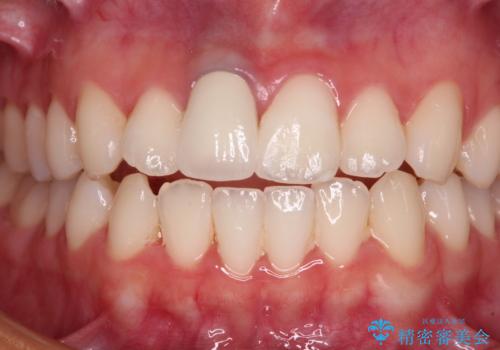

あっという間に気になっていた変色が解決し、早く治療を始めれば良かったとおっしゃっていました。

オーダーメイドタイプのクラウンを選択いただいたので、まるで天然の歯と見間違うほど自然に仕上がり、患者様には大変満足していただきました。